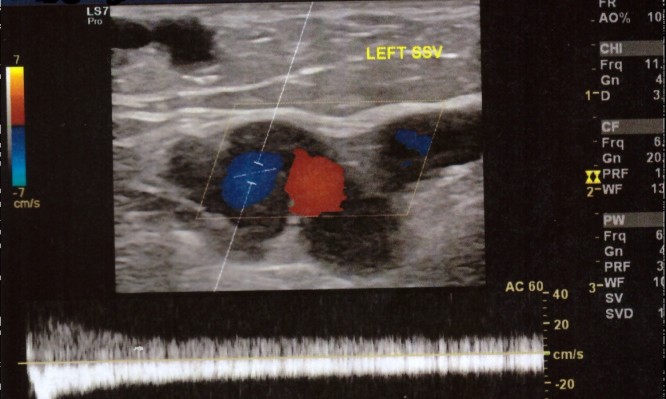

Ως το «πιο σημαντικό κομμάτι της φλεβολογίας» χαρακτηρίζει ο αγγειοχειρουργός Αλέξανδρος Ματθαίου την υπερηχογραφική εξέταση του φλεβικού συστήματος, που...